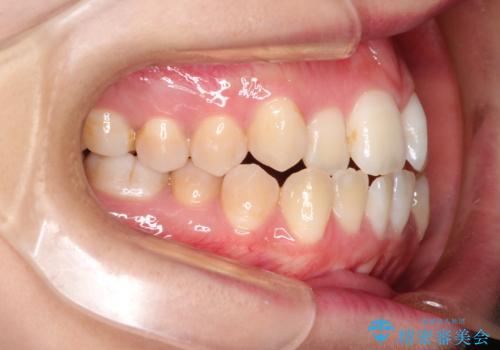

- 前歯のガタガタと、かみ合わせを改善したいとのことで来院されました。

下顎の歯が、上顎の歯に対して前方に位置していたので、下顎の歯を後方に移動させるのと、歯と歯の間を削りスペースを作り、歯を並べる計画としました。